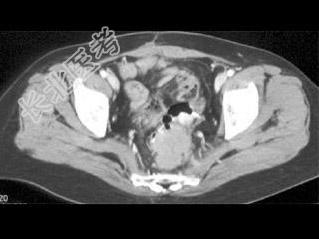

- 单项选择题患者腹痛,便血, 有卵巢癌病史,结合图像, 最可能的诊断是 ( )

A、原发性结肠癌

B、卵巢癌种植转移

C、子宫内膜异位

D、髓外造血

E、以上都不是